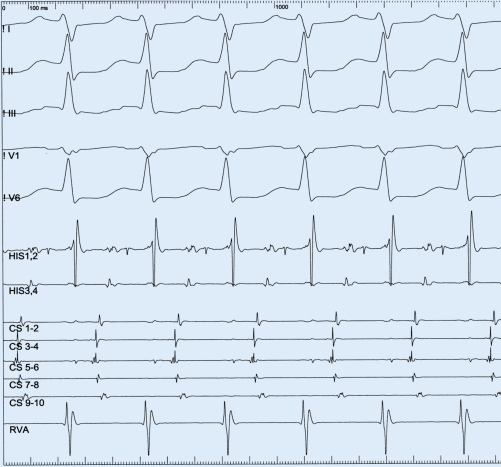

AV-Reentry-Tachykardie und Wolff-Parkinson-White-Syndrom | Herzschrittmachertherapie + Elektrophysiologie